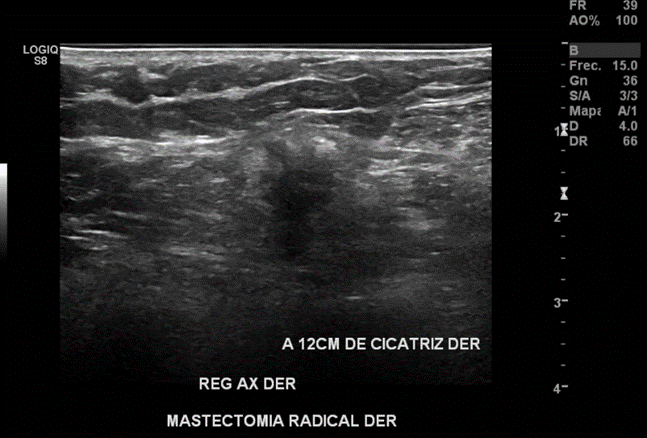

Nódulo sólido, hipoecogénico, de bordes irregulares, más alto que ancho, con sombra acústica posterior y con señal al Doppler a 12cm de cicatriz en región mamaria derecha hacia región axilar del mismo lado. Probable recidiva.

En región axilar derecha se observa imagen nodular, hipoecoica, de bordes mal definidos, de 16x12 mm.

Imagen nodular sugerente de atipia en región axilar derecha. Se sugiere estudio histológico.

BIRADS 4C.